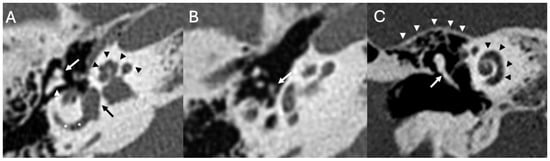

3.1. Otomastoiditis

3.1.1. Imaging

| Otomastoiditis and Otogenic Meningitis | Saat et al., 2015 [17]; Rubini et al., 2024 [18]; Vazquez et al., 2003 [19]; Bruschini et al., 2017 [20]; Barry et al., 2019 [21] | Retrospective studies, imaging reviews, and case reports | HRCT and MRI identify middle ear/mastoid infection and intracranial spread; meningitis occurs in up to 35–46% of untreated cases. |